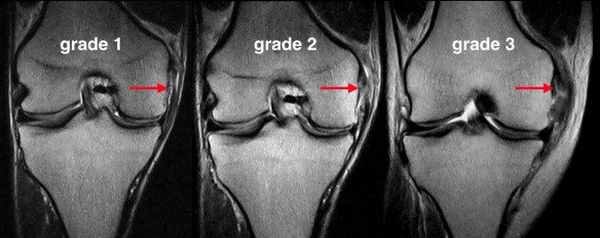

Специалисты выделяют несколько степеней повреждений коленного сустава.

- Частичный надрыв связок, который очень часто называют растяжением

- Неполный разрыв связок на колене – это надрыв связки колена, когда повреждается лишь часть волокон

- Полный разрыв коленных связок

Исходя из симптомов и клинического обследования врач ортопед может назначить такие исследования как рентгенография, магнитно-резонансная томография (МРТ), ультразвуковая диагностика (УЗД).

Рентгенография коленного сустава проводиться для исключения возможного перелома костей при травме коленного сустава. В целях диагностики разрыва коллатеральной связки при наличии симптомов нестабильности необходимо проведение функциональной (стрессовой) рентгенографии. В этом случае рентгеновский снимок сустава выполняется при отведении ассистентом рентгенолога голени пациента в сторону (медиально или латерально). Диагноз подтверждается, если со стороны разрыва коллатеральной связки отмечается расширение суставной щели. При подозрении на сочетанное повреждение околосуставных и внутрисуставных связок, менисков или суставного хряща показано проведение магнитно-резонансной томографии. При этом изображение коленного сустава имеет вид серии продольных и поперечных срезов, которые получаются в результате цифровой обработки сигналов, полученных при помощи электромагнитных волн. Магнитно-резонансная томография особенно является "золотым" стандартом для диагностики повреждения мягкотканых структур коленного сустава (хрящ, связки, сухожилия). Это совершенно безопасный и безболезненный метод исследования может быть особенно полезен при возникновении у доктора сомнений в наличии повреждения структур коленного сустава.

При первоначальном обследовании МРТ обычно не требуется. Представляется разумным проводить МРТ, если симптомы не исчезают через несколько недель консервативного лечения. Тем не менее, МРТ часто проводят при подозрении или невозможности исключить другими методами тяжелую травму или значительное внутрисуставное повреждение.